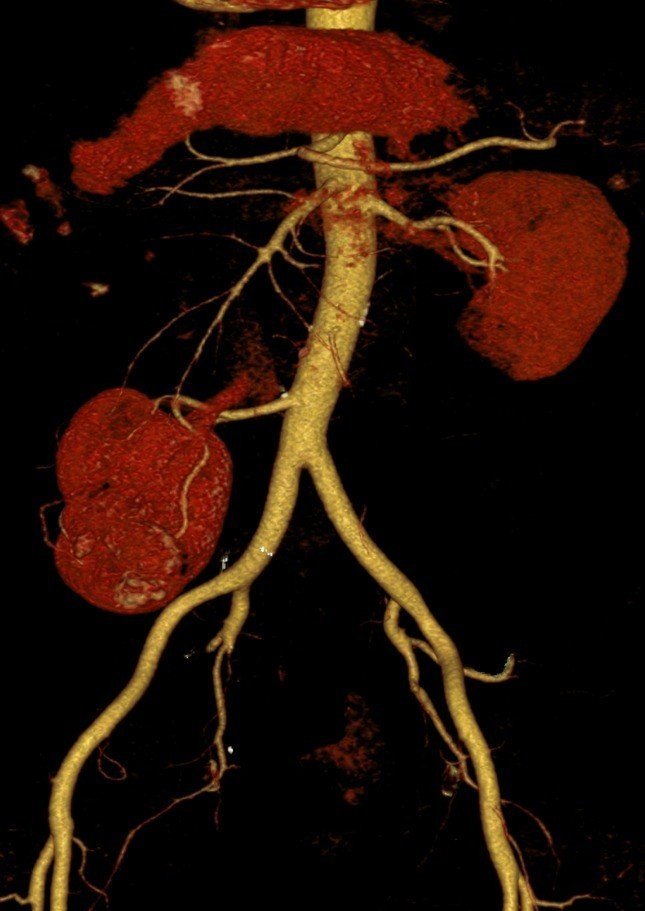

Karın ağrısı ve idrarda kan görülmesi şikâyetiyle, Trakya Üniversitesi Hastanesi Üroloji Polikliniğine başvuran ve yapılan kontroller sonrası sağ böbreğinin çok nadir görülen şekilde karnın alt kısmında, bağırsaklarının arkasında olduğu ve üzerinde bir tümör de olduğu tespit edilen 70 yaşındaki S.K adlı hasta, Trakya Üniversitesi Hastanesi'ne başvurana kadar doğuştan tek böbreği olduğunu bildiğini ve iki böbreği olduğunu öğrendiğinde şaşkınlığını gizleyemediğini belirterek, kendisini tedavi ederek hayata döndüren doktorlara teşekkür etti.

Başarıyla sonuçlanan operasyon, dünyada bir ilk olma özelliği taşıyor. Literatürde, benzer bir vak'a ile 2018 yılında Japonya'da karşılaşıldığı ve oradaki ameliyatın açık tekniklerle yapıldığı bilgisini aktaran Doç. Dr. Hakan Akdere, dünyada ikinci Türkiye'de ise ilk kez böyle bir vak'a ile karşılaşıldığını belirtti. Hastanın sağ böbreğinin, dünyada örneği çok nadir görülen bir yerde olduğunu ve bunun operasyonun önemini artırdığını hatırlatan Doç. Dr. Hakan Akdere, "Lumbal böbrekte tümörü olan bir hastayı, kapalı yöntem ile (laparoskopik) böbreği koruyarak, böbrek damarlarını geçici olarak kapatmadan ve sadece tümoral kitleyi çıkararak başarılı bir operasyonla sağlığına kavuşturup 3. gün hastayı taburcu ettik" dedi. Literatürde, 2018 yılında Japonya'da, lumbal böbrekte kitlesi olan bir hastanın açık teknik ile ameliyat edildiği ve böbreğinin tamamen alındığı bilgisi var. Dünyada daha önce laparoskopik cerrahiyle ilgili yaklaşımların mevcut olduğunu ancak böyle bir vak'ada, bu yöntemle yapılan ameliyatın ilk kez Türkiye'de, Trakya Üniversitesi'nde gerçekleştiğine ve tıp literatürüne geçecek bir yöntemle hastanın sağlığına kavuştuğuna dikkat çeken Doç. Dr. Hakan Akdere, "Böbrek tümörü tedavisinde, kanserli dokunun yayılımına göre böbreğin tamamının veya böbreği koruyarak sadece kitlenin alınması gerektiğini" vurguladı. Bu tür ameliyatları açık, Robotik Cerrahi ya da Laparoskopik cerrahi ile gerçekleştirmek mümkündür. Trakya Üniversitesi Tıp Fakültesi Üroloji A.B.D. olarak, lumbal böbrekte kitlesi olan bir hastayı, dünyada ilk kez "laparoskopik" cerrahi ile sağlığına kavuşturduk. Bu yöntem, bu tür bir vakada ilk kez uygulanan, henüz literatürde yeri olmayan bir başarıdır" ifadelerini kullandı.